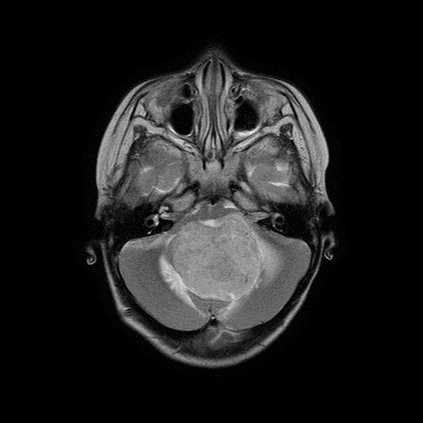

The field of explainability in artificial intelligence has witnessed a growing number of studies and increasing scholarly interest. However, the lack of human-friendly and individual interpretations in explaining the outcomes of machine learning algorithms has significantly hindered the acceptance of these methods by clinicians in their research and clinical practice. To address this, our study employs counterfactual explanations to explore "what if?" scenarios in medical research, aiming to expand our understanding beyond existing boundaries on magnetic resonance imaging (MRI) features for diagnosing pediatric posterior fossa brain tumors. In our case study, the proposed concept provides a novel way to examine alternative decision-making scenarios that offer personalized and context-specific insights, enabling the validation of predictions and clarification of variations under diverse circumstances. Additionally, we explore the potential use of counterfactuals for data augmentation and evaluate their feasibility as an alternative approach in our medical research case. The results demonstrate the promising potential of using counterfactual explanations to enhance trust and acceptance of AI-driven methods in clinical research.